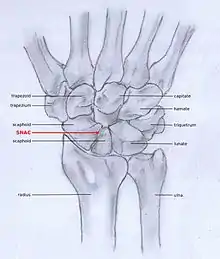

Osteoarthritis of the wrist can be idiopathic, but it is mostly seen as a post-traumatic condition.[1][2] There are different types of post-traumatic osteoarthritis. Scapholunate advanced collapse (SLAC) is the most common form, followed by scaphoid non-union advanced collapse (SNAC).[3] Other post-traumatic causes such as intra-articular fractures of the distal radius or ulna can also lead to wrist osteoarthritis, but are less common.

SLAC and SNAC are two patterns of wrist osteoarthritis, following predictable patterns depending on the type of underlying injury. SLAC is caused by scapholunate ligament rupture, and SNAC is caused by a scaphoid fracture which does not heal non-union.

SLAC is more common than SNAC; 55% of the patients with wrist osteoarthritis have a SLAC wrist.[3]